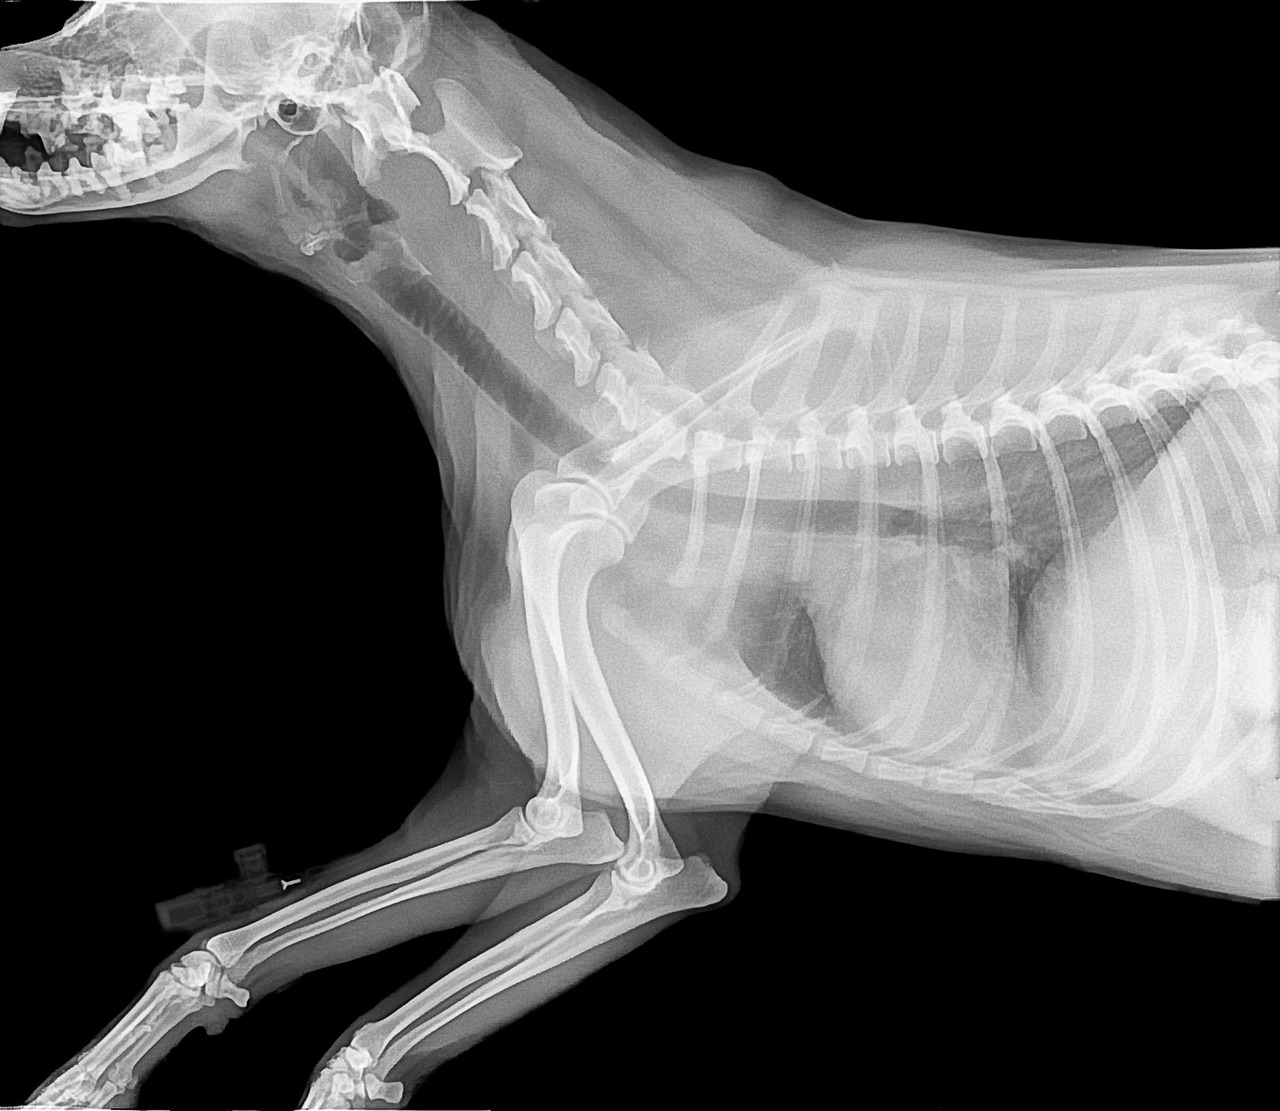

Common Symptoms of Bone Issues

Recognizing the symptoms of bone-related problems in pets can aid in early intervention and treatment. You may notice symptoms such as limping, difficulty getting up or lying down, or reluctance to engage in physical activities. Pain may not always be evident, but changes in behavior, such as increased irritability or changes in sleeping patterns, can signal discomfort. Swollen joints or lameness can indicate underlying problems such as arthritis or fractures. Additionally, watch for signs of decreased appetite or weight loss, which may reflect pain when moving. Regular veterinary check-ups can be instrumental in identifying these symptoms, especially for aging pets, before they worsen. Some pet owners may misinterpret reduced activity as a natural aspect of aging, but it’s critical to investigate these changes. Always be observant of your pet’s daily habits. If any unusual behaviors arise or if your pet appears to be in discomfort consistently, it’s time for a veterinary visit. Timely intervention can greatly improve prognosis and help prompt effective dietary adjustments and other essential treatment options.

Osteoporosis in pets can particularly pose a significant risk for older or small breed dogs and cats. This condition stems from various factors, including inadequate nutrition, hormonal imbalances, and genetics. These pets often exhibit difficulty during movements or may avoid jumping or climbing altogether due to perceived pain. Conventional treatments often include medication to manage pain and inflammation. However, integrating dietary interventions such as calcium and vitamin D supplementation can enhance the effectiveness of these treatments. Additionally, joint supplements containing glucosamine and chondroitin can support cartilage health and improve overall joint function. Regular exercise is also encouraged, as it fosters muscle strength while improving mobility. Tailoring your pet’s diet by including fortified foods or targeted supplements can significantly hinder the progression of bone-related conditions. Moreover, an enriched diet can optimize their overall health, improving vitality and reducing pain. Always follow your veterinarian’s guidelines regarding supplement types and dosages, ensuring your furry friend receives personalized care. In doing so, you’ll contribute positively toward enhancing their quality of life while addressing bone health concerns.